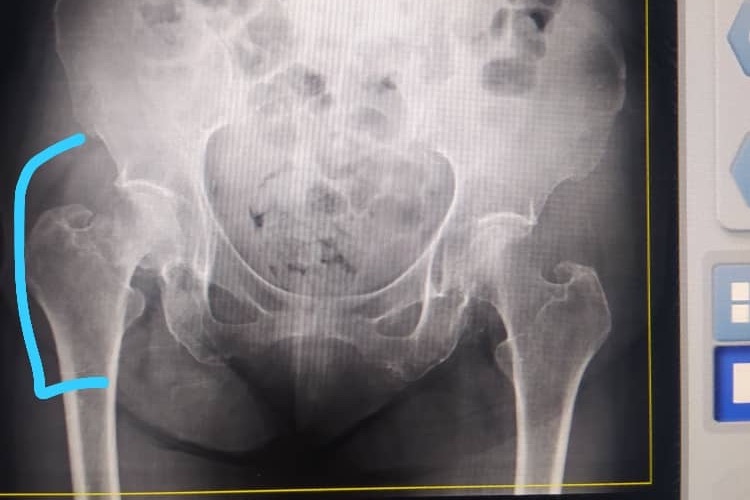

El día 02 de marzo del 2021, mi abuela se          encontraba en su casa, estaba en el baño como un día normal y al salir de este, intentó agarrarse de la puerta del baño para evitar caerse         falló en el intento y se golpeó en la pierna derecha, le dolía mucho y no podía caminar, al            llevarla hoy 03/03 a realizarse una placa nos   enteramos de que efectivamente tiene una      FRACTURA en la cabeza del fémur

No es una operación muy complicada                   únicamente necesitan dormir la pierna               derecha, operación en la que le colocarán una prótesis que le permita caminar de nuevo

No es una operación opcional ya que dentro    de los huesos se encuentra un “líquido”  o            “grasa” el cual al cabo de unas 3 o 4 semanas   empieza a entrar en la sangre llevando este       líquido hasta áreas vitales como los pulmones o el cerebro de mi abuela, lo cual podría              complicar mucho más la operación.  Tenemos un máximo de una o dos semanas para                 operarla, porque después de este tiempo el       fémur se seguirá desplazando, la cirugía se        complica más y el precio será mucho más elevado.